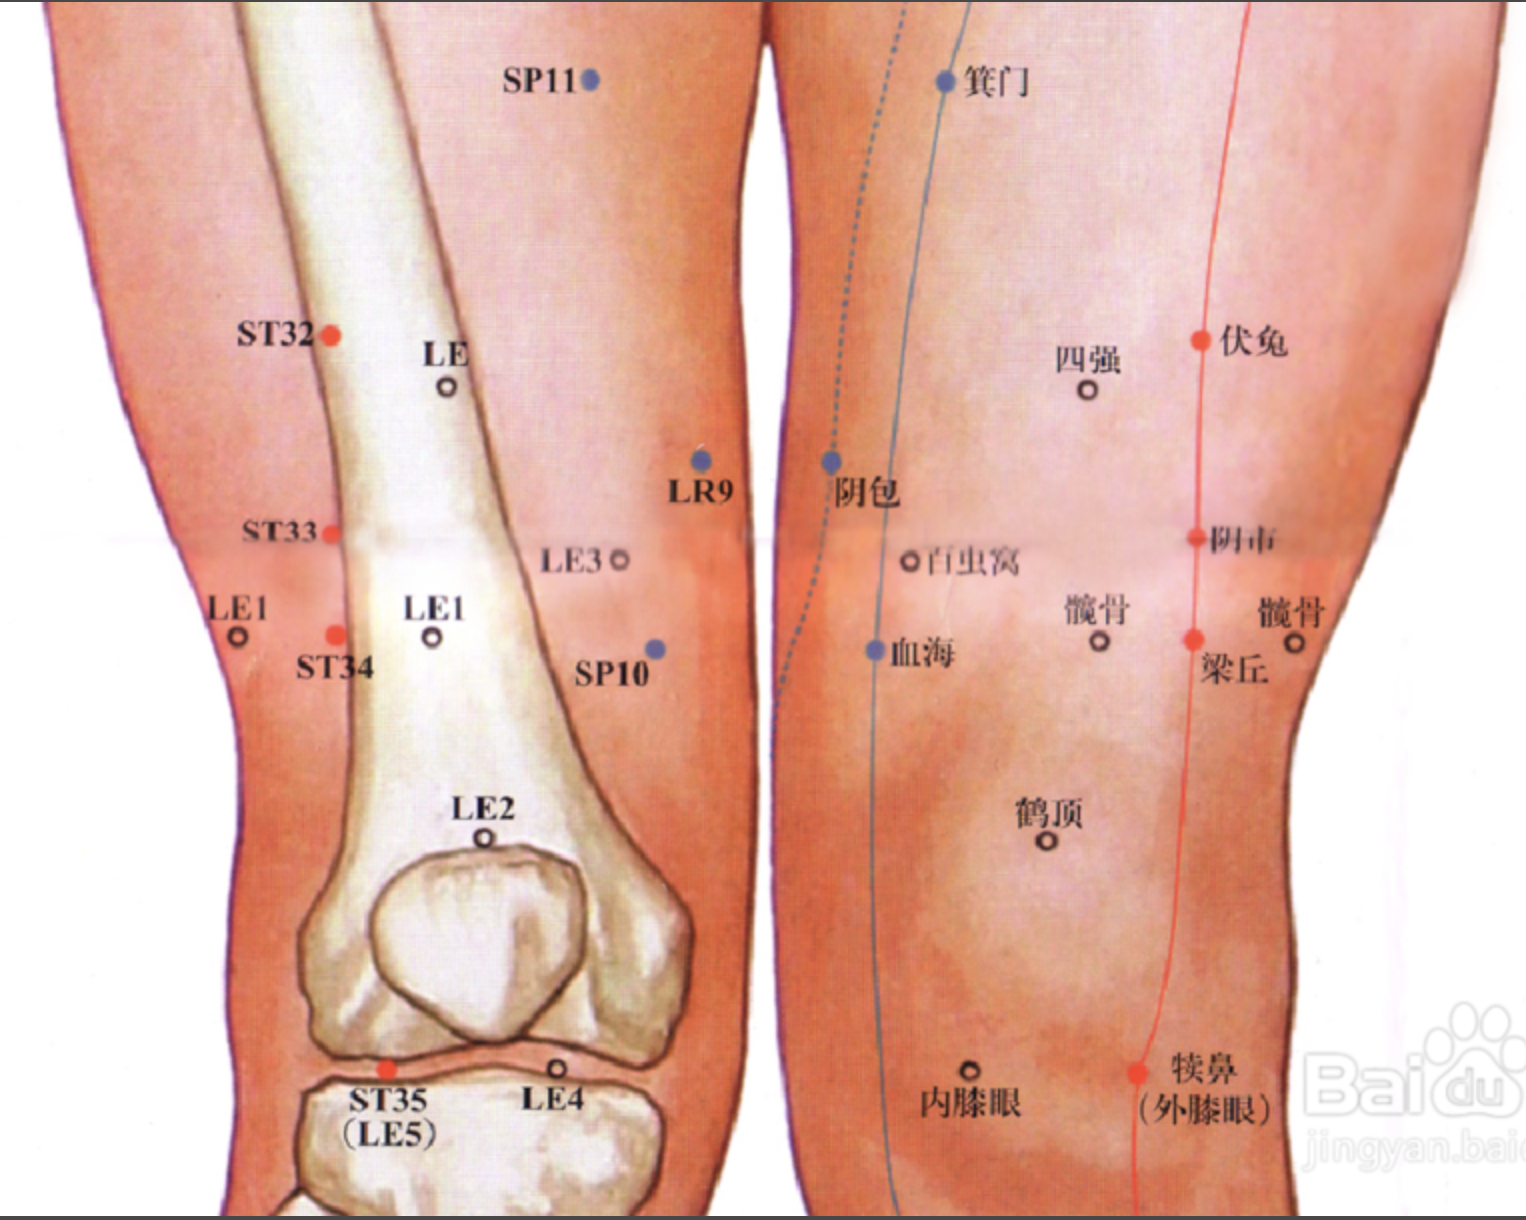

梁丘

【定位】 屈膝,大腿前面,当髂(qià)前上棘(jí)与髌(bìn)骨外上缘的连线上,髌骨上缘 2 寸。

【主治】 膝肿痛,下肢不遂,胃痛,乳痈,血尿。

【配伍】 配足三里、中脘治胃痛。

【刺灸法】 直刺 1 ~ 1.2 寸。

【附注】 足阳明经郗(chī)穴。

足三里

【定位】 在小腿前外侧,当犊(dú)鼻下 3 寸,距胫骨前嵴(jí)外 1 横指(中指)(图 10-21-4)。